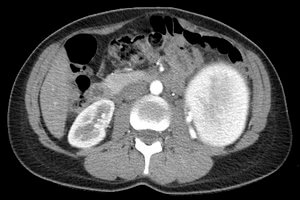

34 year old post-partum female who presented to her gynecologist with left-sided flank pain.

Comment: This post-partum patient developed a very large left renal artery aneurysm that was at significant risk for rupture. Given the size of the aneurysm and the branch of the renal artery supplying the aneurysm, we proceeded with embolization of the feeding vessel with an Amplatzer Vascular Plug. This has ultimately led to thrombosis of the aneurysm, as evidenced on subsequent follow-up imaging with ultrasound.